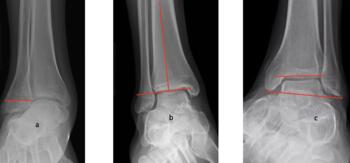

As the Ponseti grew in popularity, I noted significant discrediting of surgical options. Well long-term studies on the Ponsetti are starting to surface, and it is not without its own problems. Kids are lost to follow-up, not braced appropriately, and just like we saw in long-term studies with the posteromedial release, there is a lot of undercorrection. Casting cannot and will not ever achieve what the Cincinnati release can. Although the Ponseti may not have the complications of the Cincinnati, X-ray data reveals that the Ponseti cannot and does not correct everything, most critically, talocalcaneal angles. You can not solve a clubfoot with an Achilles tenotomy and an overly aggressive casting. As these kids develop, I see residual met adductus and calcaneal varus, along with casting complications like flat top talus and met primus elevatus. I then see that they will develop DJD just like posteriomedial and Cincinnati releases. Haasbeck and team in 1997 reported that the Cincinnatti required fewer procedures than the posteromedial release over the life of their study.14 Thomas performed a systematic review in 2019, concluding that the longer the study follow-up, the greater the relapse rate and the poorer the results of the Ponseti.15 For most of us who have done clubfeet surgery for many years, this is no surprise. Among the 46 studies meeting inclusion criteria, they saw as high as 67 percent required future surgeries to address relapse.15

So, to summarize, true congenital clubfeet have abnormal talar bodies, which lead to abnormal ankle and subtalar joints with short Achilles and tight posterior tibial tendons. Regardless of treatment, there is nothing anyone can do to make the talus a normal bone. Many of these cases can and will develop additional deformities. Only the Cincinnati release can address every issue associated with the deformity, but it is NOT a cure. The Ponseti procedure is a total compromise, also NOT a cure. The sooner everyone treats the Ponseti as a compromise, I believe we will be far happier with the outcomes. I remember discussing this with others treating pediatric orthopedic issues during the rise of the Ponseti in the early 2000s. We all agreed, undercorrecting the deformity will lead to more surgeries and residual deformities. Until we all face the reality that clubfeet are a genetic deformity and not just a positional deformity, we will never make them perfect. Thus, athletes and the military will put any and all clubfeet patients to the test. There is no doubt that exceptions exist, but in time, at least based on our limited review of over 1000 clubfeet and 250 cases we saw in the military, no one is immune to complications, arthritis, and ultimately disability.

Here is a typical case presentation. A 21-year-old Marine at Ft. Leonard Wood for training underwent a Cincinnati release at one year old and had stellar follow-up. Her surgeon even wrote her medical waiver for entrance into the Marines. She ran track in high school. She finished boot camp and completed all of her Marine training, but now has chronic pain. She no longer can run. She hasn’t passed her physical training in over a year. She developed talonavicular DJD. By all accounts, her overall clubfoot should be rated an A+; no residual deformity, normal talocalcaneal angles on AP and lateral views, no equinus, no residual varus, only slight met primus elevatus, but no signs of a flattop talus. Clinically, she lacks subtalar range of motion, which I commonly find post-clubfoot release of any kind. So many in the military do very well for a while, but the demands of the military eventually catch up to them. We all root for clubfeet to make it, but the odds are stacked against them.